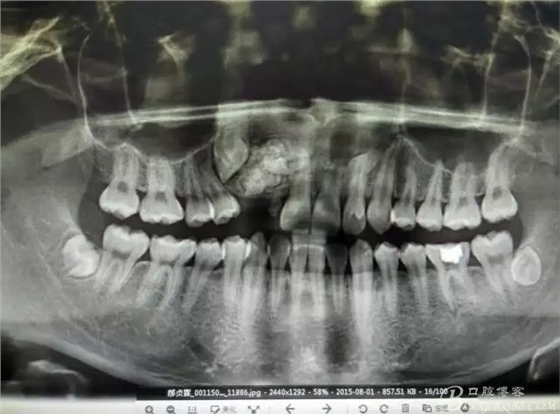

圖2.全景片影像檢查:13阻生,其冠方有重疊影像,其冠方近中上方有一巨大致密鈣化團塊。12看不見其蹤影。